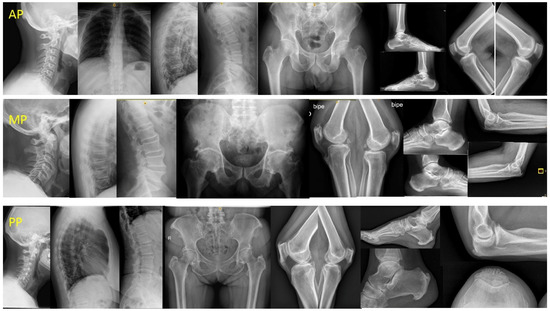

| Patterns, n 68 (%) | |

| Peripheral | 20 (29.4) |

| Axial | 21 (30.9) |

| Mixed | 27 (39.7) |